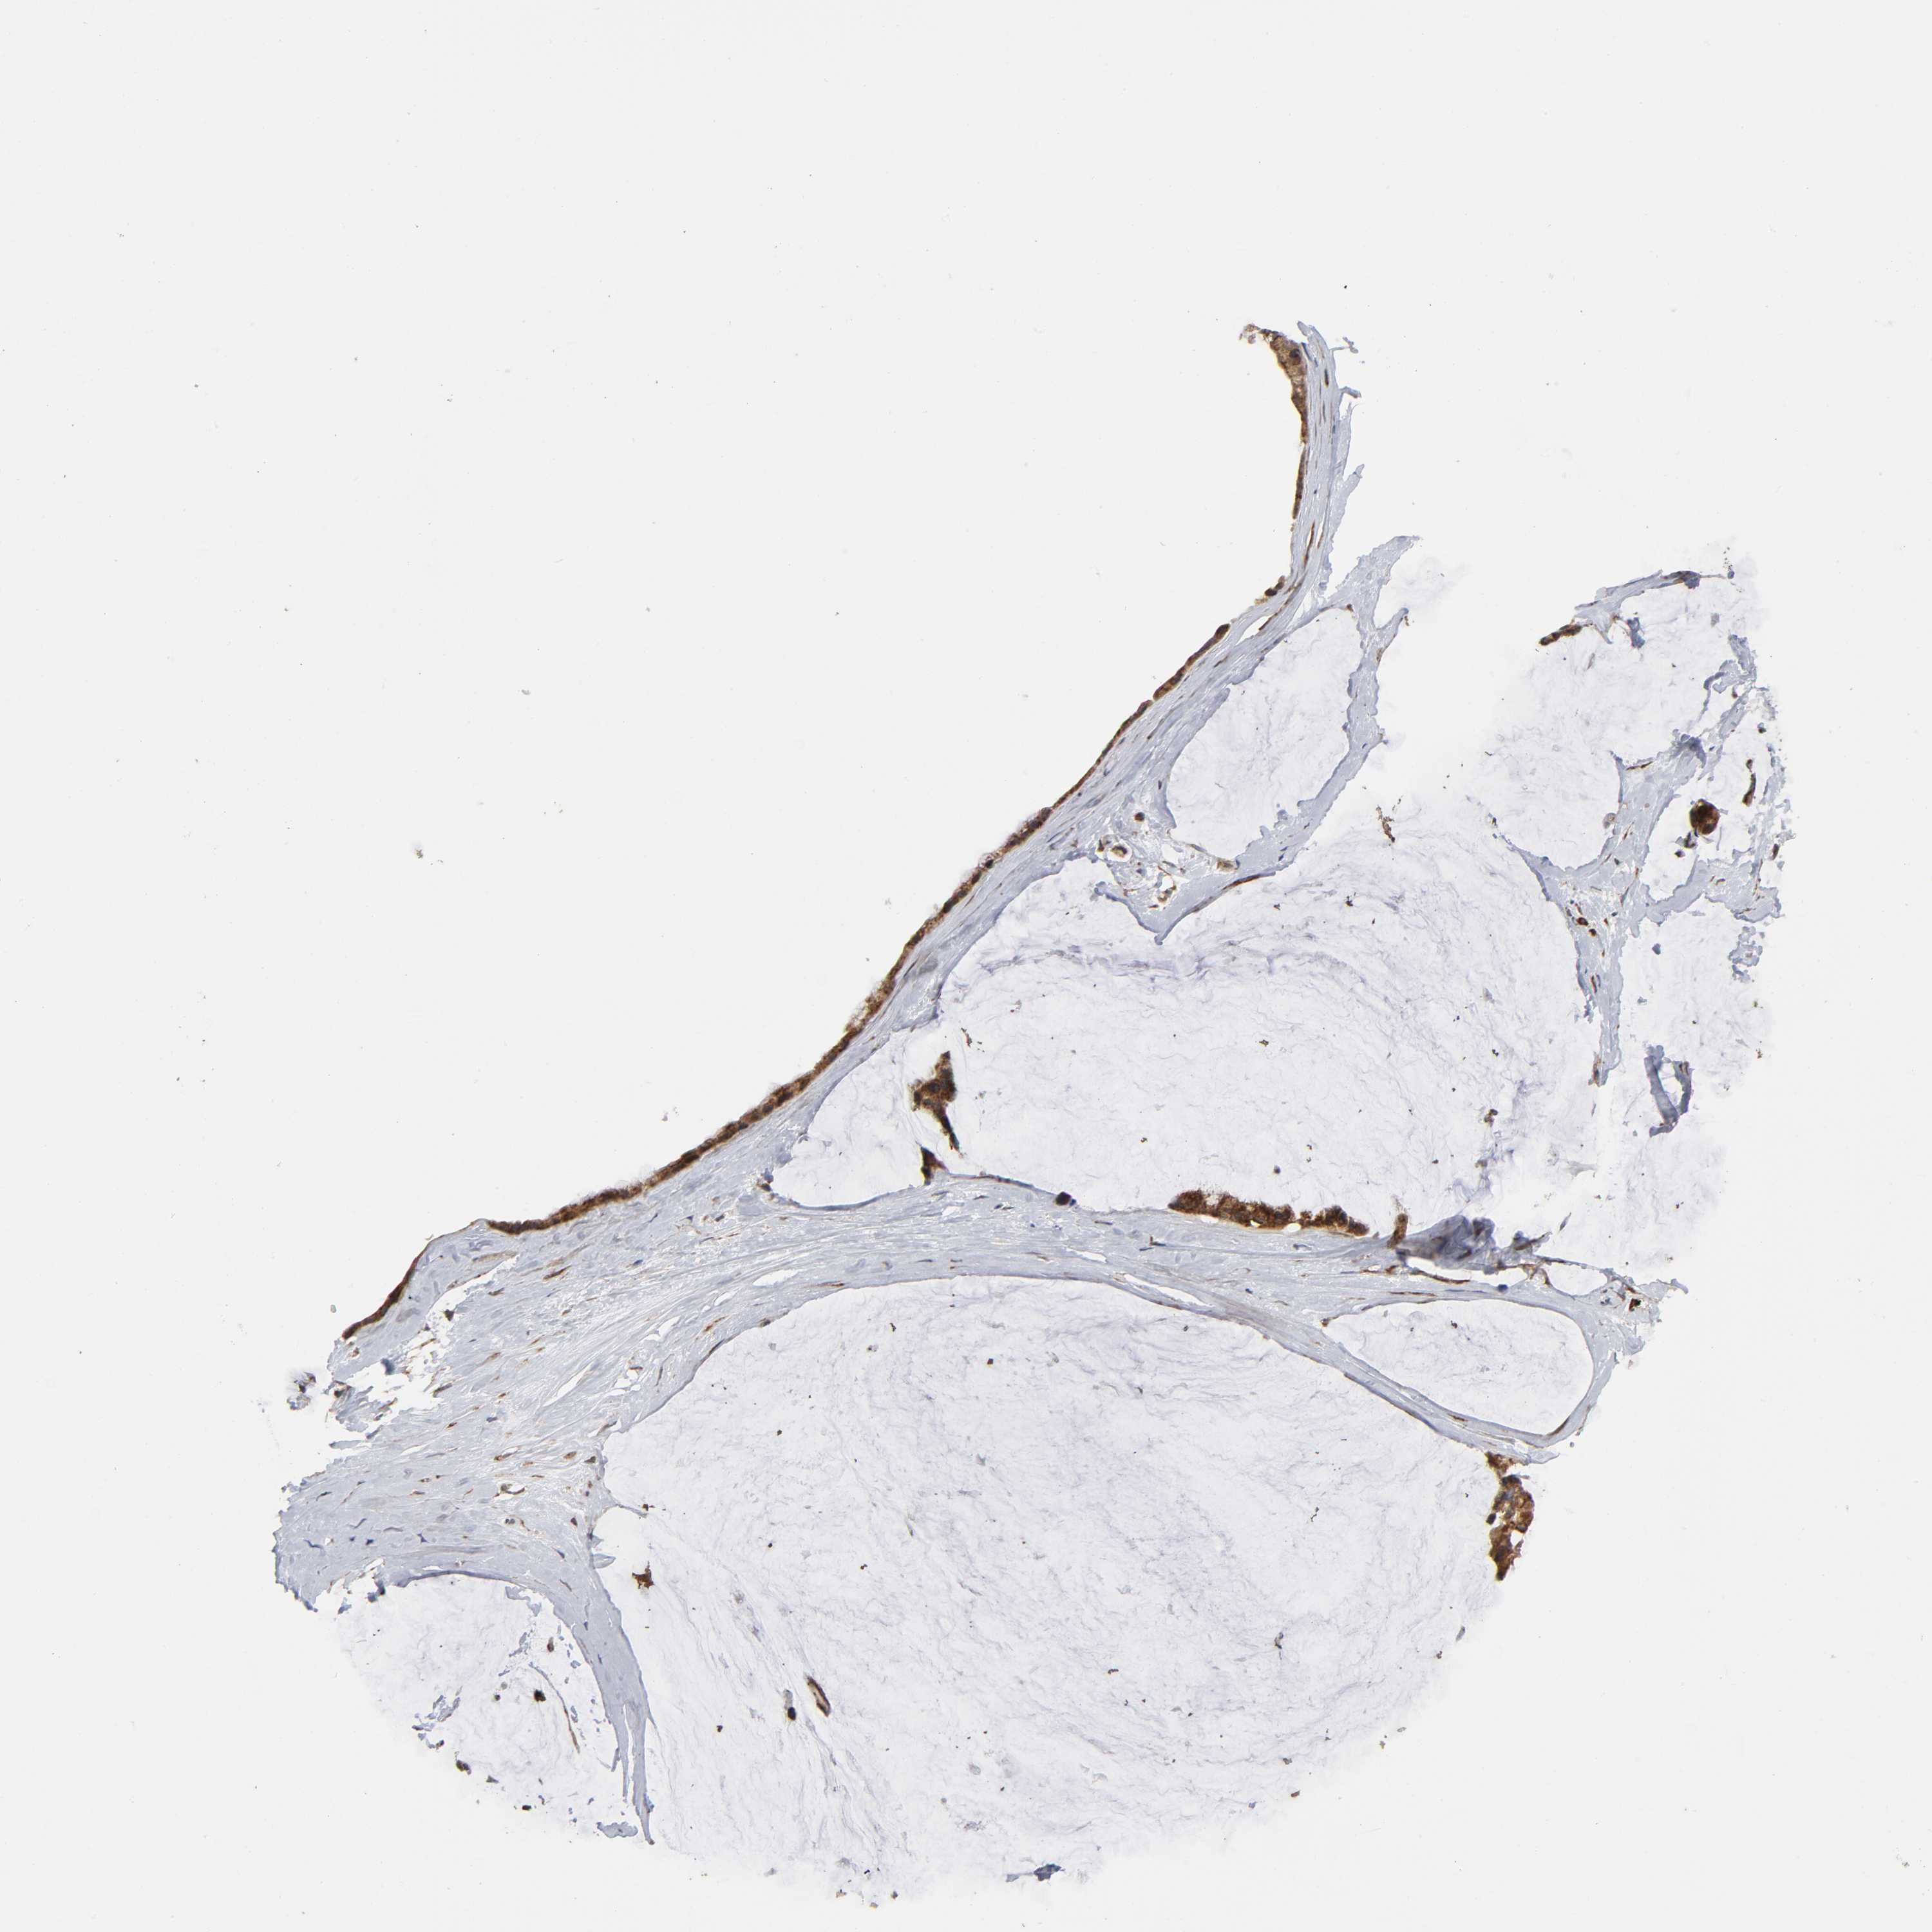

OVARIAN CANCER - Protein expressioni

A mouse-over function shows sample information and annotation data. Click on an image to view it in a full screen mode. Samples can be filtered based on level of antibody staining by selecting one or several of the following categories: high, medium, low and not detected. The assay and annotation is described here.

Note that samples used for immunohistochemistry by the Human Protein Atlas do not correspond to samples in the TCGA dataset.

Antibody stainingi

Antibody staining in the annotated cell types in the current human tissue is reported as not detected, low, medium, or high, based on conventional immunohistochemistry profiling in selected tissues. This score is based on the combination of the staining intensity and fraction of stained cells.

Each image is clickable and will lead to virtual microscopy that enables deeper exploration of all samples and also displays staining intensity scores, fraction scores and subcellular localization as well as patient and tissue information for each sample.

Antibody HPA004014

Staining

High

Medium

Low

Not detected

Intensity

Strong

Moderate

Weak

Negative

Quantity

>75%

75%-25%

<25%

None

Location

Nuclear

Cytoplasmic/membranous

Cytoplasmic/membranous,nuclear

Cystadenocarcinoma, mucinous, NOS